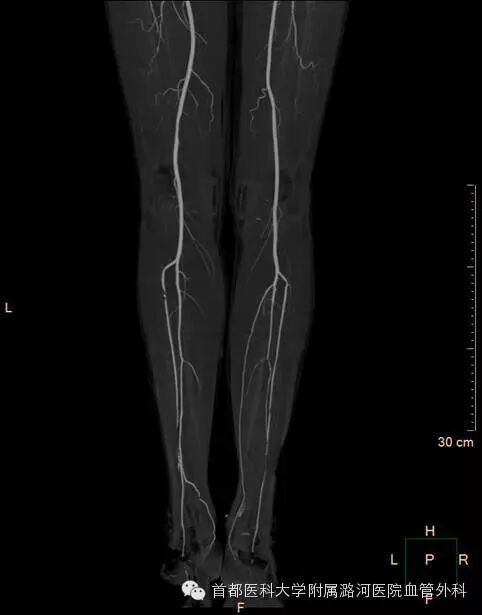

双下肢CTA:

双下肢动脉彩超:考虑右侧髂动脉起始段重度狭窄,余腔内充满低回声。